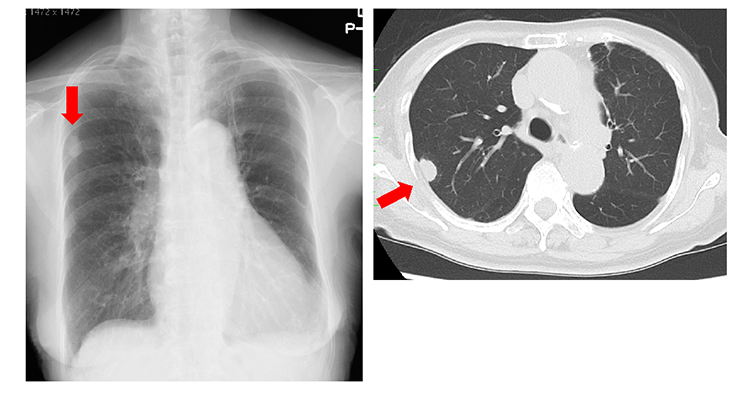

胸壁へ浸潤した原発性肺癌の胸部レントゲン写真と胸部CT。矢印は原発性肺癌が胸壁へ浸潤しているところを示しています。

一方、胸壁などにがんが浸潤したⅢ期の進行肺癌では、がんのある肺葉に加えて肋骨を含む胸壁を一緒に切除するような拡大手術を行います。